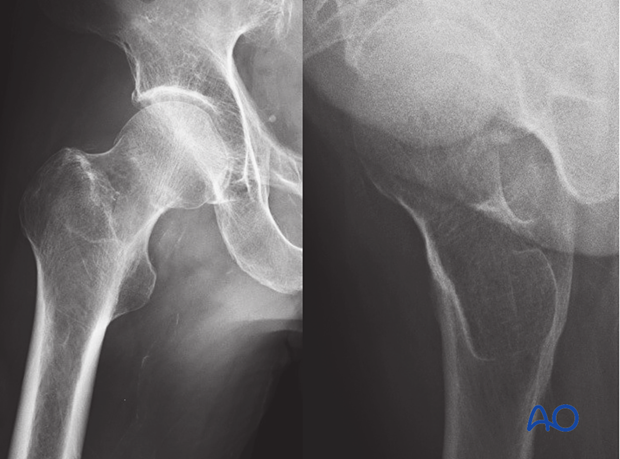

Impacted/compression fracture - Definition

The fracture occurs in the middle of a bone when it is driven into itself and buckles

Impacted/compression fracture - Cause

Compression of the bone from end to end